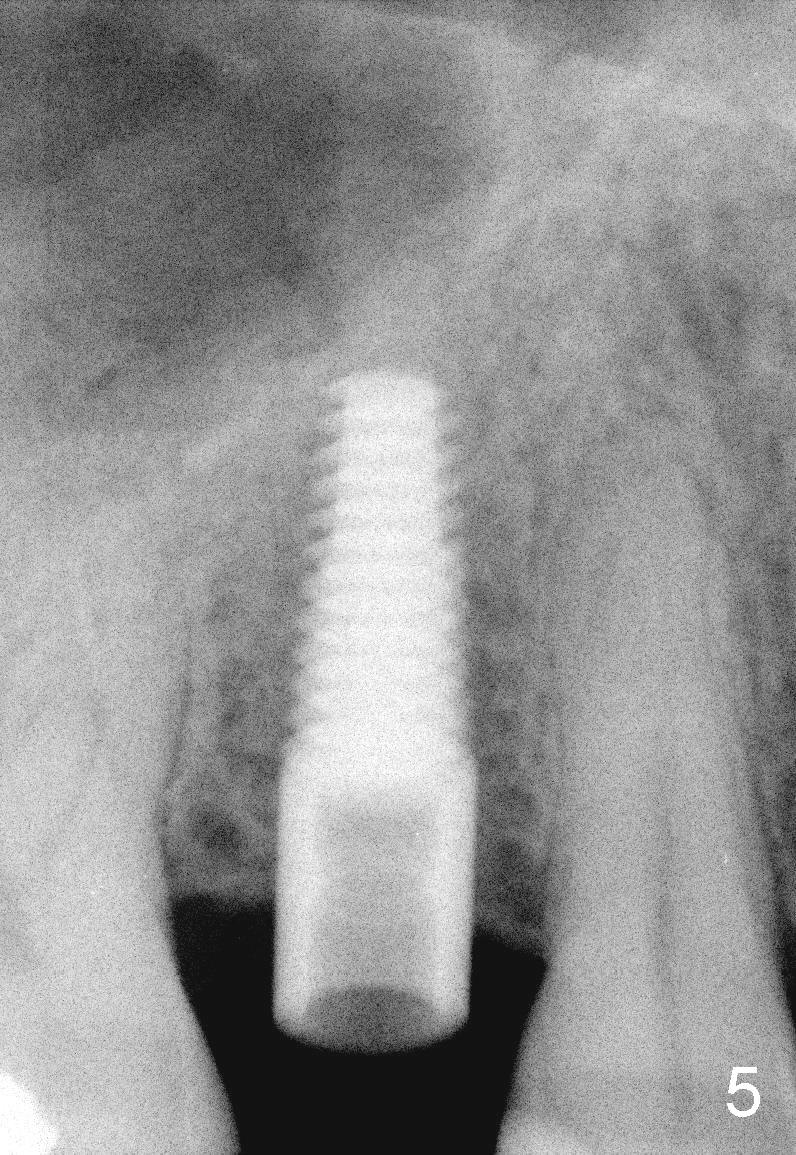

The tooth #4 was removed from a 41-year-old man (Fig.1). Fig.2 was taken 1 year and 7 months post extraction. Osteotomes (Fig.3,4) were used to create osteotomy (7 yr 9 m post ext). A 4x14 mm implant was placed below the sinus floor with insertion torque > 60 Ncm (Fig.5). The surgery was flapless (Fig.6). No antibiotic was taken pre- and post-op. The implant was found to be tender and loose. It was removed without bone graft.

Nine months later, the patient returned for re-implantation (Fig.7). Amoxicillin and Chlorhexidine were used preop and postop. Flaps were raised for better vision of reimplantation site (Fig.8). Bone density was high (type II). Drills were used to form osteotomy (Fig.9). A 4x17 mm implant was placed with internal sinus lift (Fig.10*). The insertion torque was also >60 Ncm. The flaps were approximated and a short abutment (Fig.11 A) was placed to hold perio dressing in place.